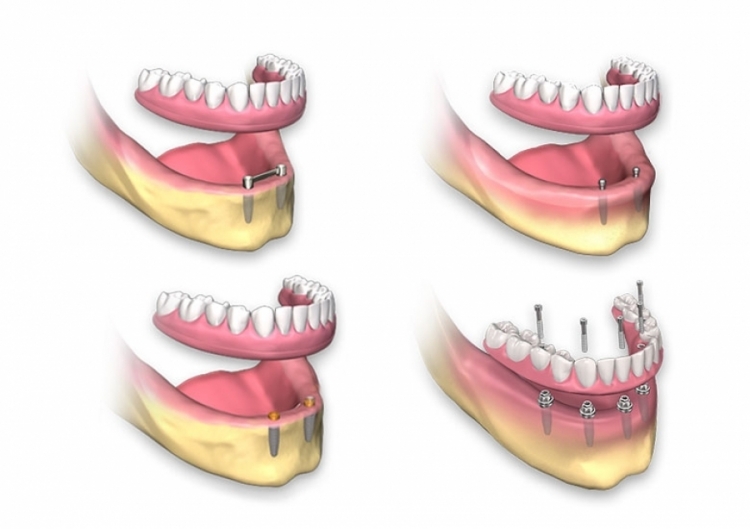

Protesi su Impianti

Protesi Semi-Fisse

Le protesi su impianti sono dentiere che si agganciano agli impianti dentali. Questi ultimi, inseriti nella mascella, permettono di creare punti di ancoraggio specifici per le dentiere.

Per realizzare dentiere su impianti nella mascella superiore è necessario installare almeno quattro impianti, mentre nella mandibola ne bastano due.

Le protesi semi-fisse offrono la possibilità di essere rimosse, facilitandone la manutenzione e la pulizia professionale.

Miglioramento delle protesi dentarie

Protesi su Più Impianti

Le dentiere supportate da impianti sono ideali per chi ha perso un’intera arcata di denti, sia superiore che inferiore.

Molti impianti dentali fungono da ancoraggio per una dentiera personalizzata, garantendo stabilità e prevenendo problemi come lo scivolamento o il disagio.

Si possono usare 2, 3, 4 o più impianti, in acrilico, perfettamente stabili, rimovibili individualmente per la pulizia e dotati di una barra di ritenzione implantare.